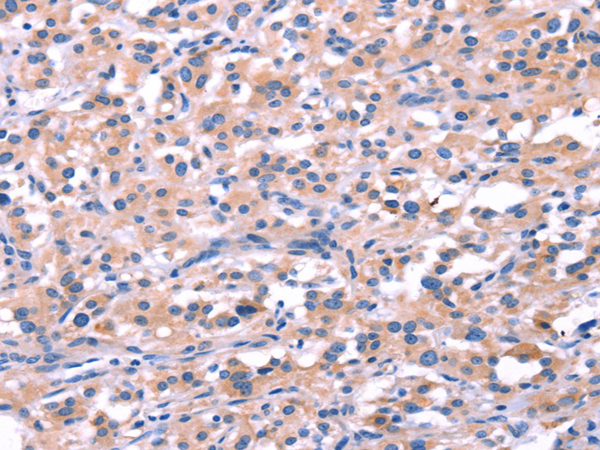

Immunohistochemistry of paraffin-embedded Human thyroid cancer using FEM1B antibody diluted at 1:20

Immunohistochemistry of paraffin-embedded Human thyroid cancer using FEM1B antibody diluted at 1:20